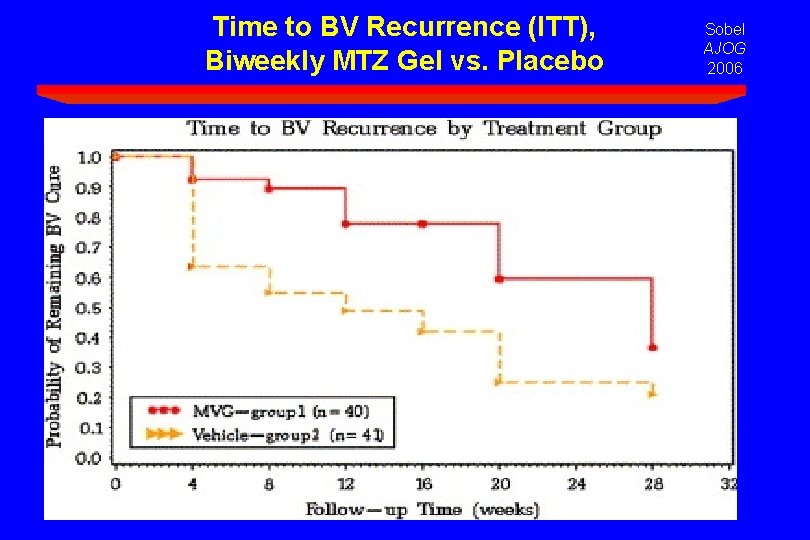

Time to BV Recurrence (ITT), Biweekly MTZ Gel vs. Placebo Sobel AJOG 2006